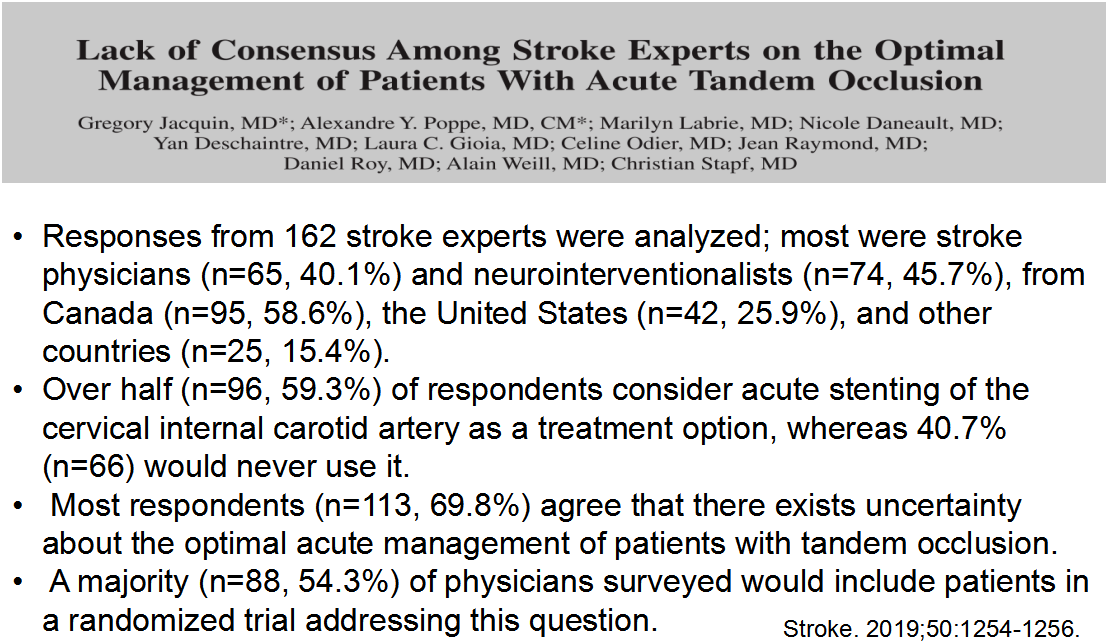

1. 先处理MCA还是ICA

2. ICA支架还是不支架

3. 串联闭塞溶栓后介入的安全性